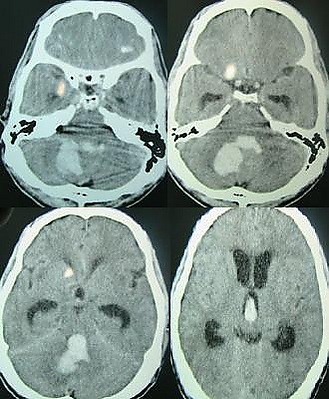

Методом выбора в диагностике внутримозгового кровоизлияния является компьютерная томография головного мозга, позволяющая не только определить наличие внутримозговой гематомы, но и оценить её локализацию, распространённость и объём, выраженность отёка мозга и степень дислокации. Для диагностики небольших гематом в стволе мозга и изоденсивных веществу головного мозга («несвежих») гематом предпочтительна магнитно-резонансная томография.